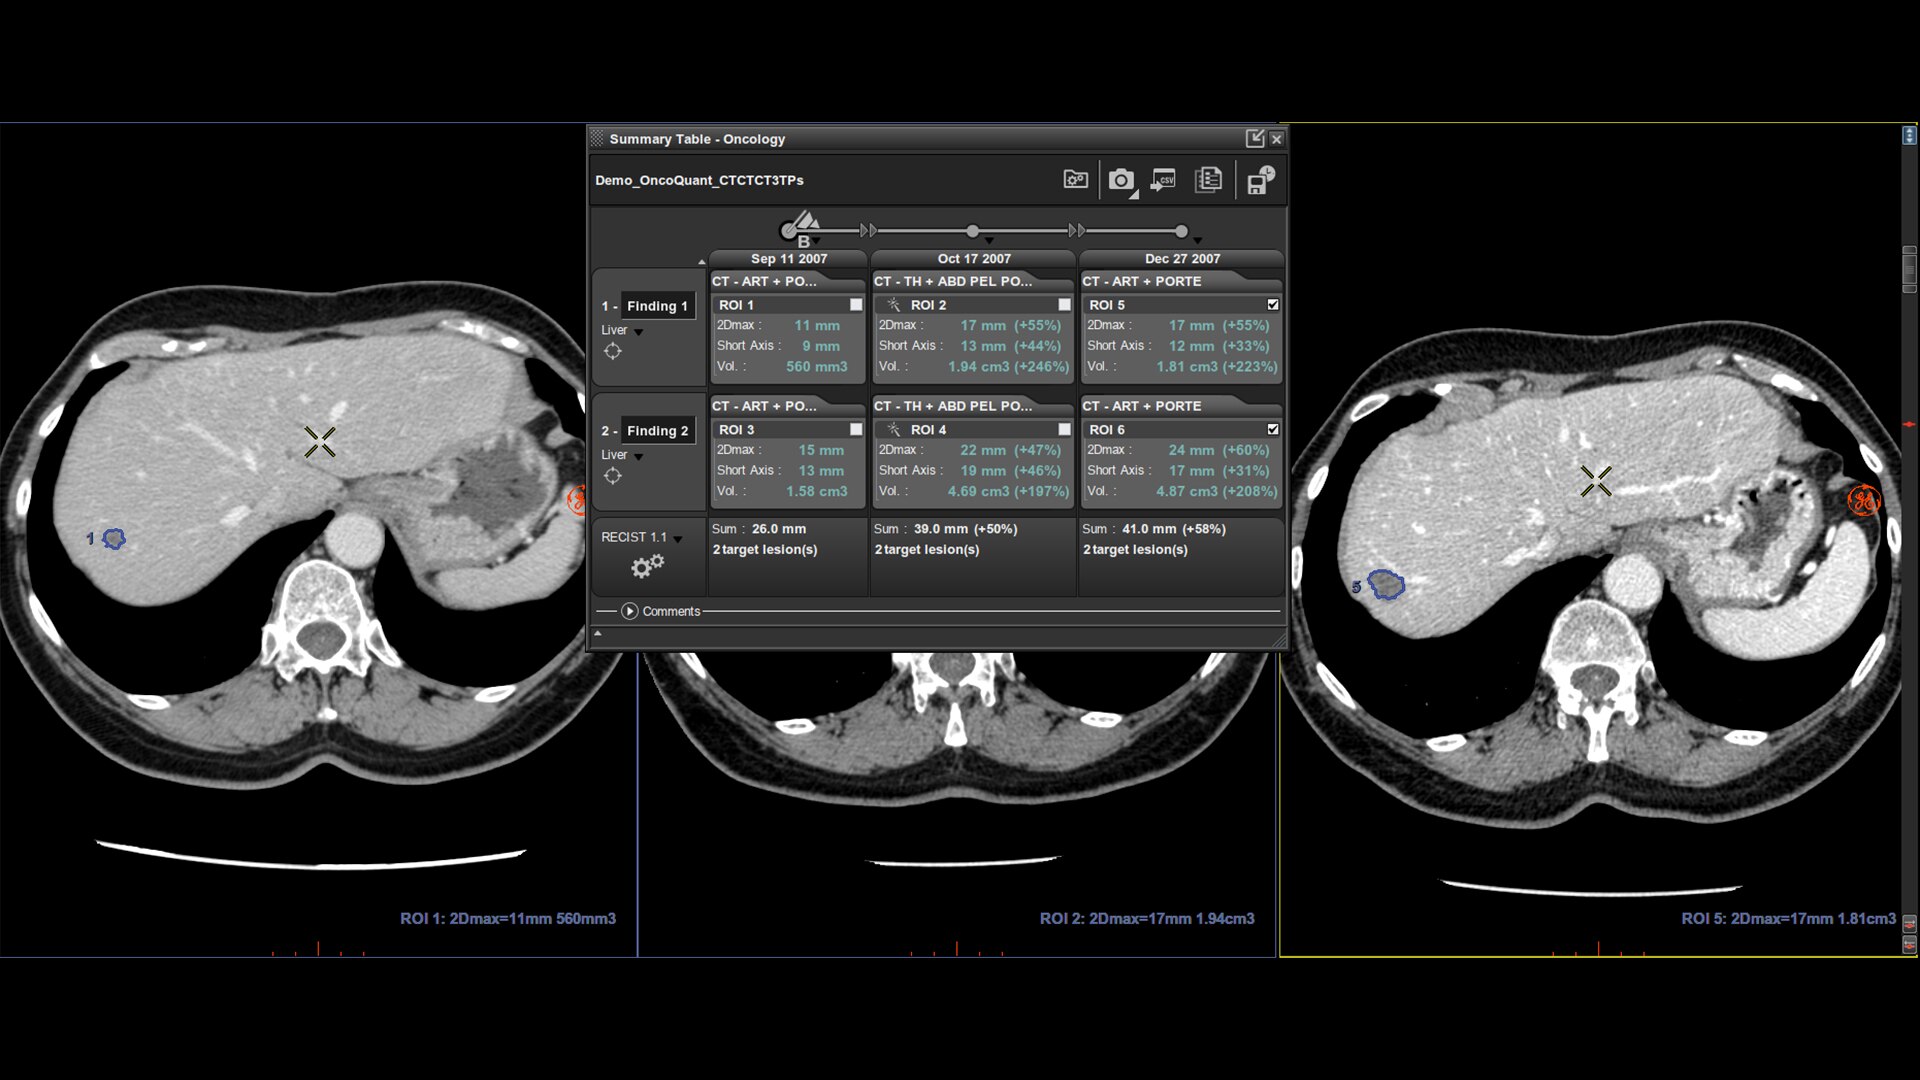

Breast Care Pathway

Invenia ABUSは、乳がん診療で診断から治療まで乳房画像診断の トータルソリューションを目指します

スクリーニング(検診)

一定のワークフロー、時間で、効率的な乳房超音波検査を提供します。

診断

ボリュームデータだからできるバーチャルスキャンや多断面読影により正確な診断をサポートします。

治療計画

乳房の3次元像での提供で正確な病変の位置特定を支援し、より的確安心な治療計画を支えます。

経過観察

再現性の高いABUSボリュームで過去画像と比較することで、治療効果を見守ります。